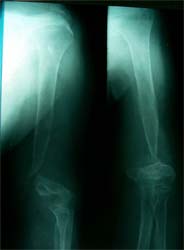

肱骨骨折骨不连6年,大段骨缺损,经异型钢板内固定、植骨,骨生长因子 和骨髓细胞注射方法,成功修复骨缺损